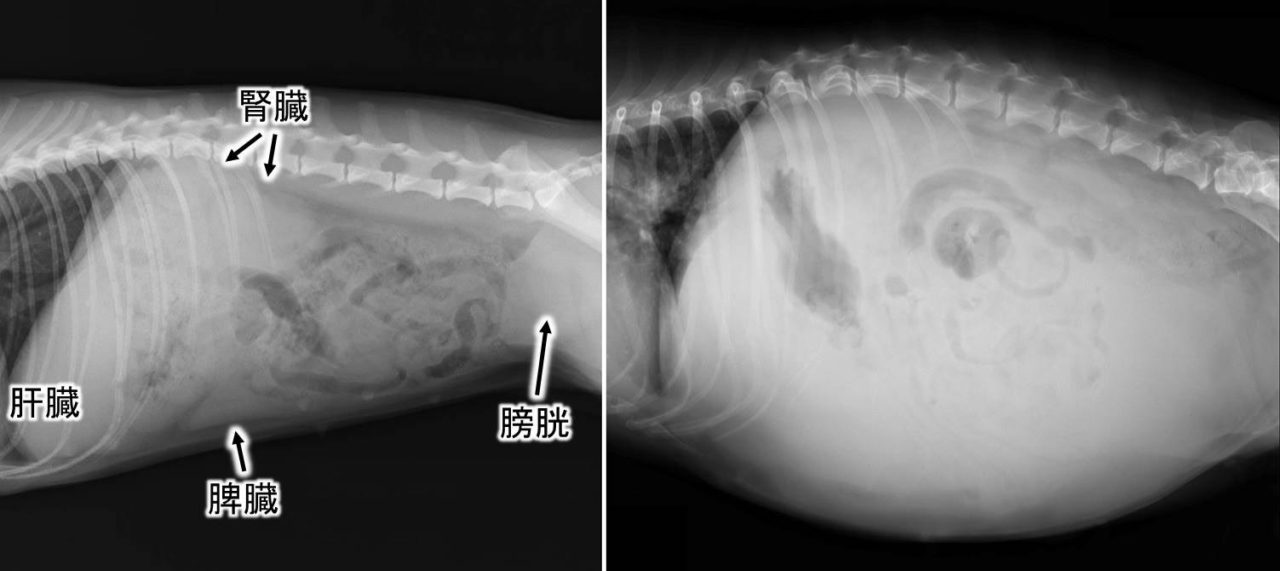

腹水とは、腹腔内に液体が異常にたまった状態を指します。

健康な猫では腹水はほとんど存在せず、たまっている場合は何らかの病気が関係している可能性が高いです。

猫の腹水の見分けポイント

腹水が疑われる場合、次のような特徴が見られることがあります。

- お腹全体が張ったように膨らむ

- 左右対称に膨らんで見える

- 触ると中で液体が動く感じがする

- 体重が急に増えたように見える